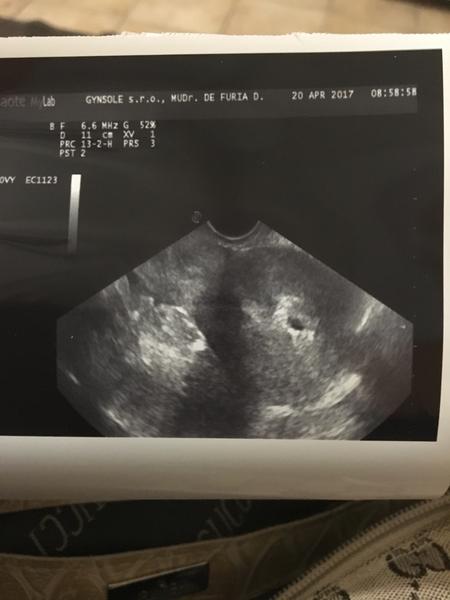

prosím Vás, dnes mi lekár potvrdil tehotenstvo (pridávam foto zo sona), som 7+5. Povedal mi, že tam je aj druhý vak, ktorý nevedel identifikovať a objednal ma znovu. Predpísal mi hormonálne tabl.

Chcem sa Vás popýtať, kto mal podobnú fotku zo sona v tomto rannom štádiu a boli to zdravé dvojičky? Kľudne mi píšte ak to aj nedopadlo dobre.

Ten druhy vak ma byt napravo od toho co vidno dobre? Lebo ja tam vidim iba jedno babo (to kde vyznacil CRL)